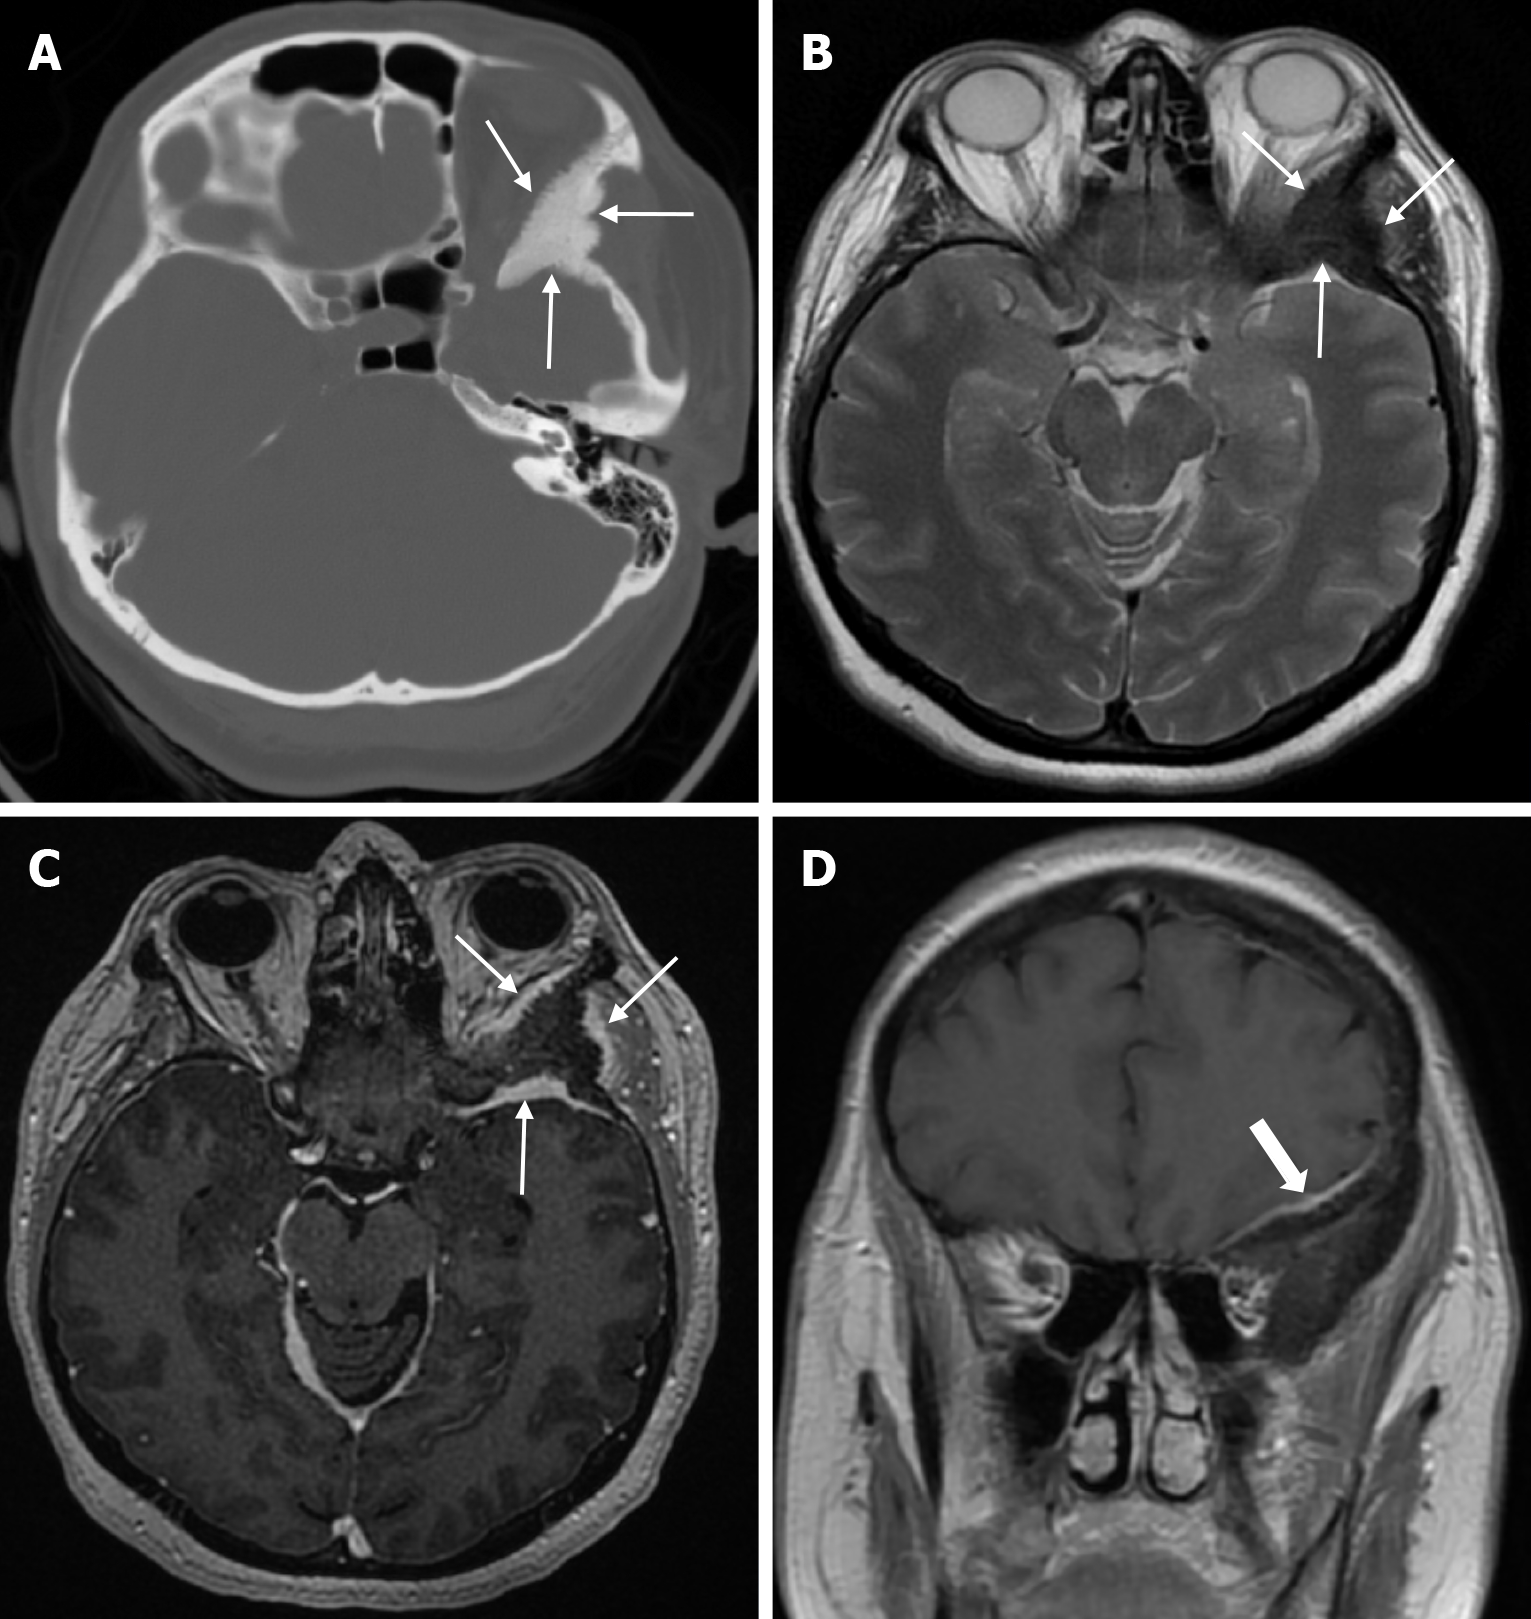

Arachnoid granulations (Pacchionian granulations) are cerebrospinal fluid-filled projections that extend from the subarachnoid space through openings in the dura into the venous sinuses and can be seen macroscopically. Their incidence varies from 0.3% to 55%. Arachnoid granulations are usually seen in millimeter dimensions, but may grow to fill the dural sinuses or arch the inner table[11]. In addition, intraosseous arachnoid granulations can sometimes extend to the inner table of the bone, causing scalloping, remodeling or bone erosion of the inner table[12]. The prevalence of arachnoid granulations increases with age, but there is no difference in gender distribution. Arachnoid granulations with a slight left hemispheric predominance are found in the dural venous sinuses, most frequently in the transverse sinuses and especially in the middle or lateral parts. The second most common location is the superior sagittal sinus, but they can be found anywhere in the dural venous sinuses. Arachnoid granulations are usually detected incidentally. If they fill and expand the dural sinuses, causing partial sinus obstruction, they may cause symptoms of increased intracranial pressure due to venous hypertension. They are usually associated with headaches. Arachnoid granulations may be seen as radiolucent areas on plain radiography of the skull or may cause compression on the inner table of the skull. On CT imaging, arachnoid granulations can be seen as sharply demarcated, hypodense structures in close relation to the dural venous sinus. On MRI, they usually show hyperintense signal on T2-weighted images and hypointense or isointense signal on T1-weighted images compared to brain parenchyma (Figure 1). On CT angiography, MR angiography or catheter angiography imaging, arachnoid granulations appear as oval or round filling defects in the dural venous sinuses during the venous phase[11]. Recent advances in radiology have made it possible to identify brain herniations into the arachnoid granulation by improving image quality with higher resolution and thinner slice three-dimensional T1-weighted and T2-weighted MRI sequences (Figure 2). Brain herniation into the arachnoid granulation is rare in the literature, and the incidence of brain herniation into the calvarial or dural sinuses has been reported to be 0.32%[13]. Arachnoid granulations may be confused with pathological processes in the dural venous sinuses[11]. In the differential diagnosis of arachnoid granulations, venous sinus thrombosis, dural-based tumors, or structures such as septa and fat that may cause filling defects in the dural venous sinuses should be considered[12]. Dural sinus thrombosis usually fills an entire sinus segment or several sinuses and may extend to the cortical veins, whereas arachnoid granulations appear as focal and well-defined defects. Fresh thrombus in the dural sinuses are hyperdense on CT and hyperintense on T1-weighted MRI. Differential tumor diagnosis can be made based on its shape, lack of contrast enhancement and diffusion restriction[11].

Epidermoid cysts are small or medium-sized, benign, and slow-growing tumors that arise from the remnants of ectodermal cells in the bones of the skull. These cysts can also develop after trauma or surgery. Epidermoid cysts are lined with squamous epithelium. They contain deposits of cholesterol and keratin. These cysts constitute less than 1% of primary intracranial tumours, while intradiploic epidermoid cysts account for less than 0.25% of intracranial tumours. These tumors can occur at any age from the first decade of life to the seventh decade, with a mean age of 32-38 years, and there is no gender predilection. Epidermoid cysts are most commonly found in the frontal, parietal and occipital regions and often involve more than one bone. Epidermoid cysts appear on plain radiography as round or lobulated lytic areas with smooth and sclerotic margins. On CT they appear as non-contrast enhanced intradiploic lytic hypodense lesions with smooth sclerotic borders. Epidermoid cysts often cause remodeling and widening of the inner and outer tables. Epidermoid cysts that appear hyperdense on CT due to bleeding, calcification or high protein content are called white epidermoids and are observed quite rarely. On MRI, epidermoid cysts appear isointense/hyperintense on T2-weighted and fluid-attenuated inversion recovery (FLAIR) images and slightly hyperintense on T1-weighted images (Figure 4). These lesions restrict diffusion on diffusion-weighted imaging but show no contrast enhancement on contrast enhanced sequences[19].